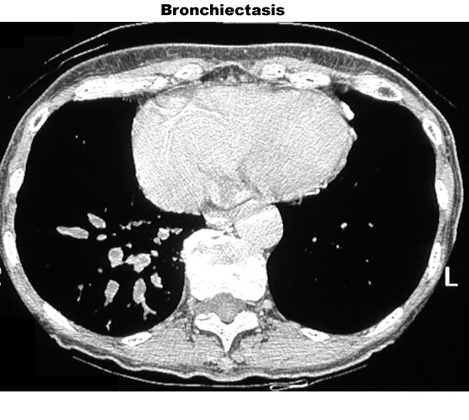

Bronchiectasis

Dilated bronchi with peribronchial fibrosis, visualized in various cuts of CT as cystic spaces, tubular shadows and branching densities.